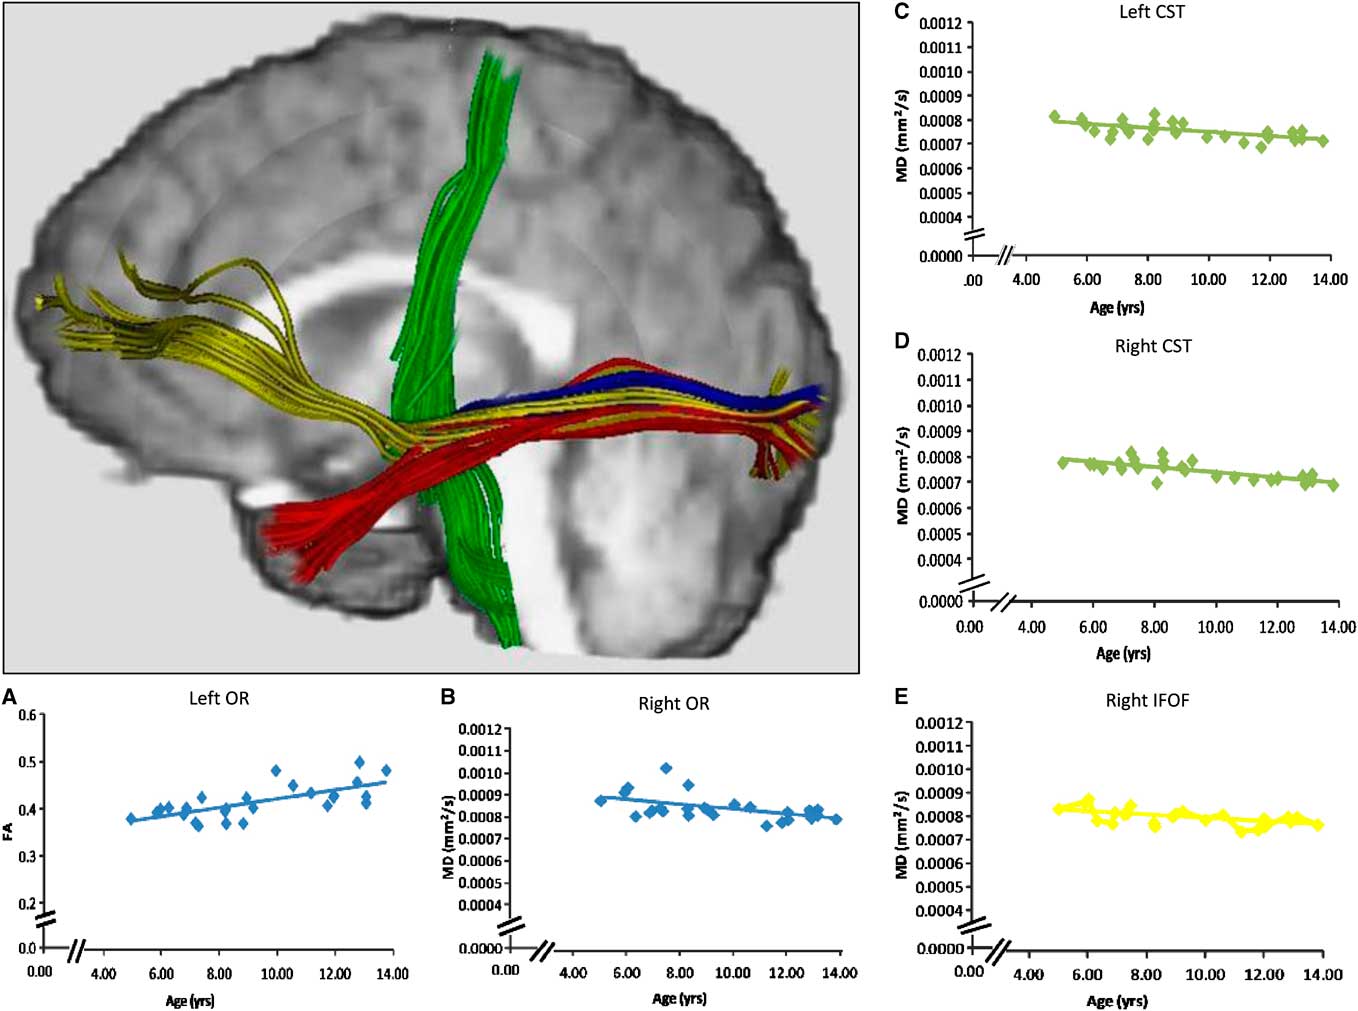

We examined the optic radiations because visual inputs are sent via this tract to visual cortex and hence it is important in visual motor responding (Figure 1). Imaging studies have described a pathway running between the ventro-medial occipital and orbito-polar frontal cortex as the inferior fronto-occipital fasciculus (Catani, Howard, Pajevic, & Jones, Reference Catani, Howard, Pajevic and Jones2002; Forkel et al., Reference Forkel, Thiebaut de Schotten, Kawadler, Dell'Acqua, Danek and Catani2012), and a tract connecting the occipital and the anterior temporal lobes as the inferior longitudinal fasciculus (Figure 1) (Catani, Jones, Donato, & Ffytche, Reference Catani, Jones, Donato and Ffytche2003). We examined the inferior fronto-occipital fasciculus and the inferior longitudinal fasciculus as they both project from the occipital lobe to other brain regions, and have been implicated in two functional paths—the dorsal and ventral streams (Loenneker et al., Reference Loenneker, Klaver, Bucher, Lichtensteiger, Imfeld and Martin2011; Urbanski et al., Reference Urbanski, Thiebaut de Schotten, Rodrigo, Catani, Oppenheim, Touze and Bartolomeo2008). Finally, because a motor response reflected completion of the reaction time task, we also examined the primary efferent tracts for voluntary motor function: the cortico-spinal tracts (Figure 1). We recognize that these white matter connections are not exhaustive in terms of visual-motor processing, but believe that they provide a solid foundation for examining relevant brain networks underlying information processing speed.

Fig. 1 Tractography of the optic radiations (blue), the inferior fronto-occipital fasciculus (yellow), and the inferior longitudinal fasciculus (red), each seeded from anatomical landmarks. The cortico-spinal tracts (green) were seeded from MEG activations. Probabilistic tractography was used to create regions of interest to calculate DTI measures, but streamline tractography was used on a representative subject in this image for visualization purposes. Age-related changes in FA and MD were observed for the optic radiations of the left and right hemispheres, respectively (scatterplots A, B). Age-related changes in MD were also detected bilaterally in the cortico-spinal tracts (scatterplots C, D), and in the inferior fronto-occipital fasciculus of the right hemisphere (scatterplot E).

Age and white matter change

Mean and standard deviations for FA, MD, RD, and AD of each white matter connection are reported in Table 1. FA and RD of the optic radiation in the left hemisphere, and FA and MD of the optic radiation in the right hemisphere changed significantly with age in this cohort (Table 2 and Figure 1). Furthermore, MD and RD decreased with age in the inferior fronto-occipital fasciculus of the right hemisphere, and bilaterally in the cortico-spinal tracts (Table 2 and Figure 1). The quadratic term for the RD of the inferior fronto-occipital fasciculus of the right hemisphere was the only variable that added unique variance beyond that of the linear term. As no age-related changes were apparent in the inferior fronto-occipital fasciculus of the left hemisphere and bilaterally in the inferior longitudinal fasciculus, these connections were not considered in further analyses.